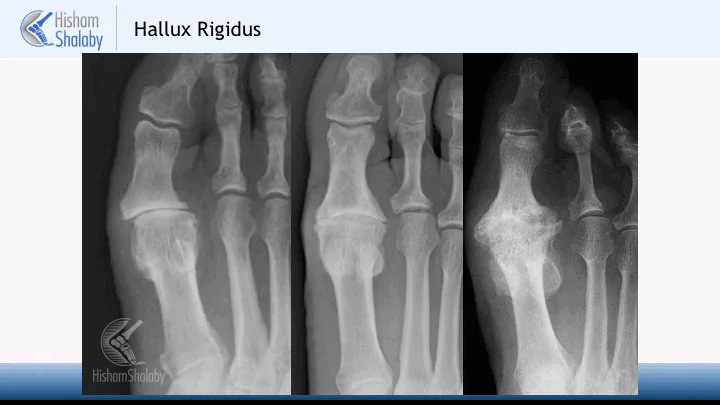

Hallux Rigidus is a term used to describe wear and tear (arthritis) in the joint at the base of the big toe.

Over many years, the joint forms new bone, to increase its surface area, which contributes to the bony swelling felt around the joint. This also causes the joint to be stiff.